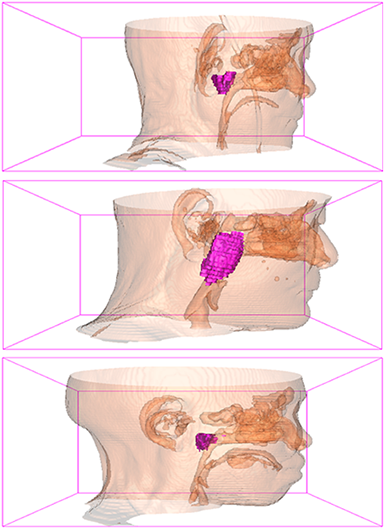

Comparison with ground truth. Some predicted results of MMFNet are shown in 2D images and 3D images in Figure 7 and Figure 8. As shown in these figures, although the shape and size of NPC are varied from each other, MMFNet can still accurately determine the regions of NPC and obtain the accurate contours of tumors. Through analyzing 2D images in figure 7, MMFNet has a capacity to fuse multi-modality MRI to reduce the confusion brought by intensity’ similarity between nearby tissues and NPC. The values of , and of MMFNet are shown in Table 1. MMFNet can reach the best results with , and .

Comparison with related works. Table 1 reports the values of , and for different methods. Predicted masks of different methods are illustrated in Figure 9 and Figure 10, which respectively present results in 2D and 3D images. Through comprehensively analyzing these results, the proposed MMFNet actually have the following properties:

(i) It directly fuses 3D MRI images rather than 2D slices. Thus, it can effectively use meaningful information from neighboring slices of MRI to realize NPC segmentation. As shown in Table 2, MMFNet can bring , and improvements in and compared to the best method based on 2D images (Multi-modality patch-based CNN). And Figure 10 shows that 3D-based methods have less isolated regions (false positives) than 2D-based ones.

(ii) It segments NPC by fusing multi-modality MRIs with the multi-encoder network. Thus, it can learn complementary and interdependent features from different modalities of MRI for final decisions. Additionally, comparing with input-level fusion networks and decision-level fusion networks, layer-level fusion networks (including MMFNet) can effectively capture informative features from different modalities of MRI and fuse low-level features and high-level features.

(iii) It uses a fusion block to fuse low-level features from different modalities of MRI and prepare these low-level features for the fusion with high-level features. Thus, it can more effectively fuse information from various sources. It also uses the self-transfer strategy to initialize the netwerk. Hereby, it can stimulate encoders to make full mining of meaningful features from modality-specific MRI. And it finally improve base multi-encoder-based network (Merging encoders’ fetures) by , and in and .